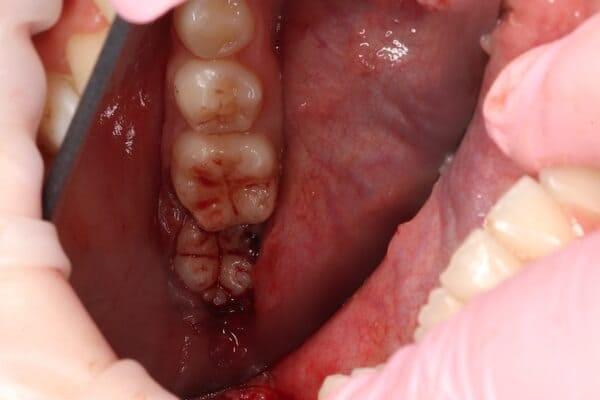

Видалення зубів мудрості. Бродик Богдан.

Видалення зубів мудрості — досить складна процедура, яка потребує високої кваліфікації хірурга. Особливо це стосується ситуації, коли видалення проводиться в ранньому віці. У даному випадку дівчинці 11 років було проведено видалення двох зубів мудрості. Перевага такої тактики полягає в тому, що зуби мудрості видаляються до того, як вони починають негативно впливати на прикус. Це дає дуже багато переваг для формування зубо-щелепної системи, але потребує майстерності лікаря.

Видалення зубів мудрості. Бродик Богдан.

Часто чуємо питання: чи можливо за один візит видалити всі зуби мудрості одномоментно. Так, це можливо, і є ситуації, коли це більш раціонально, ніж розділяти такі маніпуляції на чотири окремі візити. Але в такому випадку це потрібно робити в умовах анестезіологічного забезпечення. У даному клінічному випадку, завдяки ефективній взаємодії з анестезіологічною командою, було проведено одномоментне видалення чотирьох зубів мудрості. Тепер пацієнтка скерована до ортодонта і готова розпочинати ортодонтичне лікування.